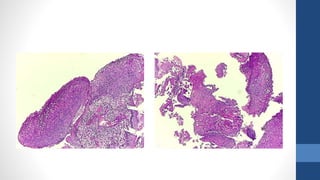

Mujer de 23 años, biopsia de cervix

Diagnóstico

•LIE de alto grado, NIC 2

• El precursor directo del cáncer cervical es la lesión de alto grado (también conocido

como NIC 2 y NIC 3) el cual puede progresar a cáncer en un periodo de hasta 10 ó

más años. La mayoría de lesiones de bajo grado desaparecen sin tratamiento o no

avanzan, sobre todo en mujeres jóvenes. Sin embargo, los casos que ocurren en

países en donde no hay programas de tamizaje en funcionamiento y la enfermedad

ha estado presente durante periodos de tiempo más largos, son menos probable de

regresionar o desaparecer.